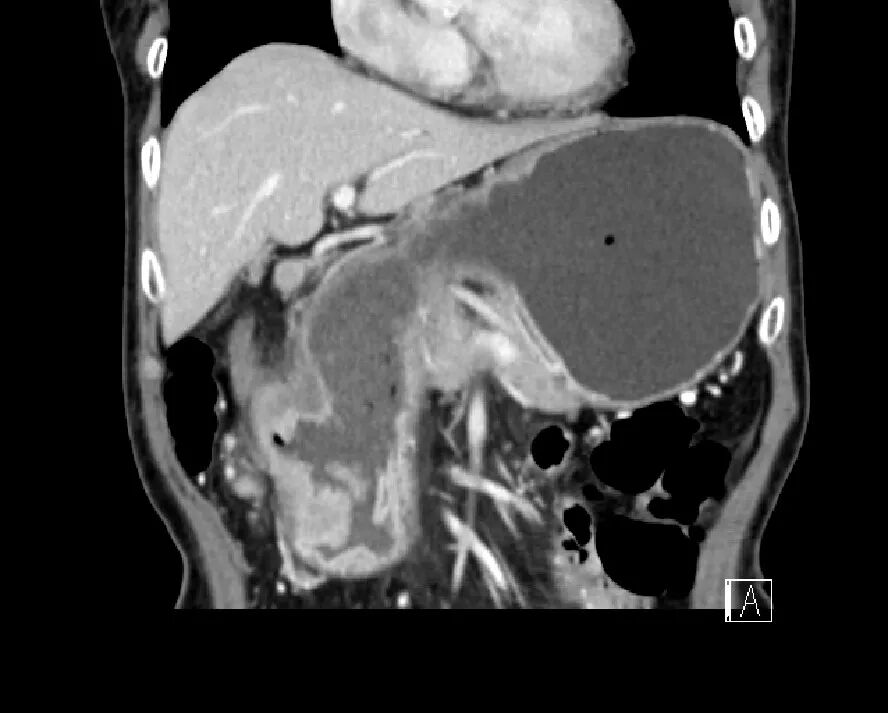

脾挫裂伤

病因病理

脾挫裂伤主要是指腹部受到外在力量的撞击而产生的闭合性损伤,是常见的腹部严重创伤,多由高处坠落、交通意外等引起。

临床表现

患者可有患部疼痛,但严重者多以失血性休克、腹部膨隆为首发症状。